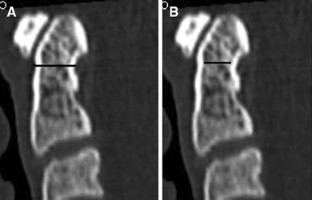

Computed tomographic (CT) scans of 88 adult patients (aged 18–78 years) were analyzed; 40 patients (45%) were male (mean age: 43.08 years) and 48 (55%) were female (mean age: 43.39 years). The minimum external and internal anteroposterior and transverse diameters of the odontoid process on sagittal and coronal planes were measured on CT multiplanar reconstructions of the cervical spine.

The mean value of the minimum external anteroposterior diameter was 10.83 ± 1.08 and 7.53 ± 1.10 mm for the minimum internal anteroposterior diameter. The mean value of the minimum external transverse diameter was 9.19 ± 0.91 and 6.07 ± 1.08 mm for the minimum internal transverse diameter. The mean AP diameter was significantly larger than the mean transverse diameter; 57 (65%) individuals had the minimum external transverse diameter >9.0 mm that would allow the insertion of two 3.5-mm cortical screws with tapping, and five (6%) individuals had the minimum internal transverse diameter >8.0 mm that would allow the insertion of two 3.5-mm cortical screws without tapping.